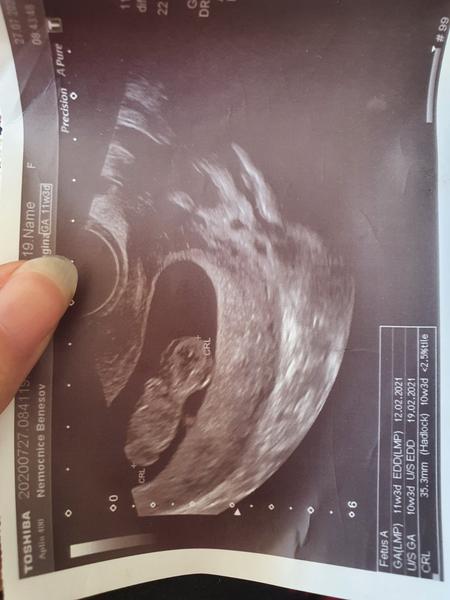

Krásný večer dámy slečny, je možné že na fotce ultrazvuku vidím obličej miminka nebo se mi to zdá? Fotka z ultrazvuku je 10+1

Jasne, je to takova lebecka zepredu... Casto nechapu, proc lekari tyhle fotky davaji, za me to vypada desive, kdyz je ta fotka obliceje zepredu 😀